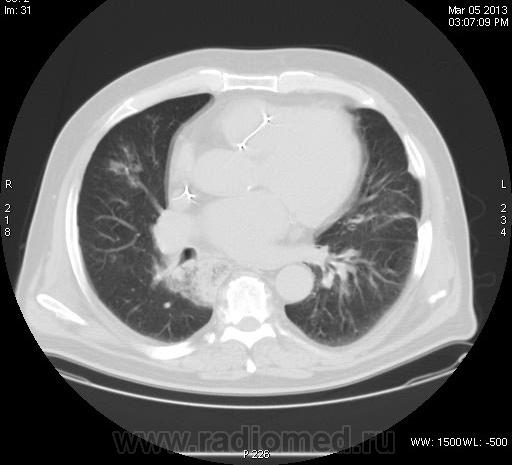

Непонятка КТ ОГК.

Задыхается, кашляет, Т-37, КТ "Cito!", рентгенограмм нет. В поликлинике закл.:" Двухстороння пневмония, МТС?"

Анализ изображений КТ исследования ОГК обязательно должен проводиться в двух окнах (легочном и медиастинальном). А в диф. плане, так еще  и с контрастированием. Есть ли возможность хотя бы увидеть изображения во втором режиме: для оценки участков консолидации, наличия кавтации, оценки л/узлов и средостения в целом...?

зон консолидации и лимфоузлы средостения. Похоже на саркоидоз. Тогда у  пациента не должно быть особых жалоб.

Не повезло больному. 11.03.2013г. умер в реанимации, сегодня только узнал. Причина смерти- множественные инфарт- пневмонии?!. Завтра выложу все, что найду. Я в шокеsurprise! Писал диссеминацию по типу септической + БАР.

Что говорить о контрастном КТ исследовании, если даже КТ-изображения данного пациента не выставлены во втором (медиастинальном) окне; была бы возможность оценки характера участков конолидации легочной ткани, состояния лимфатических узлов и средостения в целом.  Почему то никто не отметил наличие катеторов в верхней полой вене и правом желудочке сердца, что косвенно должно было навести на тромбоэмболический процесс. Конечно, в данном случае, КТ исследование с болюсным контрастированием помогло бы в правильной диагностике.